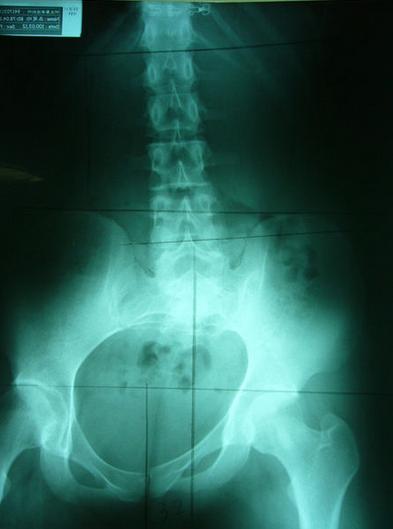

理想骨盆相对位置:两边骨盆、股骨头对称等高、中线穿过腰椎荐椎与耻骨联合、骨盆环呈现对称心形